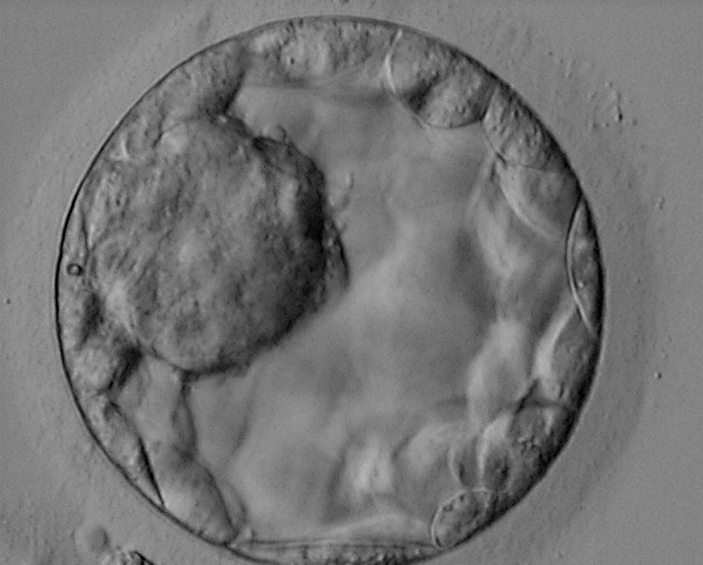

Бластоциста человека на 5-й день развития. Внешняя неклеточная оболочка — зона пеллюцида. Фото с сайта atlas.eshre.eu

По эмбриону на такой стадии тоже сложно что бы то ни было сказать о человеке, который из него вырастет. Можно только приблизительно разглядеть, из каких клеток он получится. Бластоциста на такой стадии (на 5-й день развития и далее до имплантации) состоит из двух слоев клеток, разделенных полостью с водой: трофобласта (внешний плотный слой; см. Trophoblast) и внутренней клеточной массы (внутренний рыхлый слой). Трофобласт собственно к зародышу имеет мало отношения, он впоследствии превратится в зародышевые оболочки и частично — в плаценту. Внутренняя клеточная масса же поделится еще на два слоя: эпибласт (верхний) и гипобласт (внутренний, прилежащий к полости). Последний тоже войдет в состав зародышевых оболочек, и только из эпибласта вырастет непосредственно человек.

Бластоцисту не видно ни на каких УЗИ. Мы знаем о том, как она выглядит, только потому, что можем ее вырастить в лаборатории. Так и делают в рамках экстракорпорального оплодотворения — доращивают эмбрион до бластоцисты и потом переносят в матку будущей матери. Строго говоря, это последняя стадия эмбриогенеза человека, которую можно рассмотреть in vitro, потому что искусственную матку (которая поддерживает все стадии развития) до сих пор не вырастили, и в лаборатории эмбрион полноценно пройти имплантацию не может.